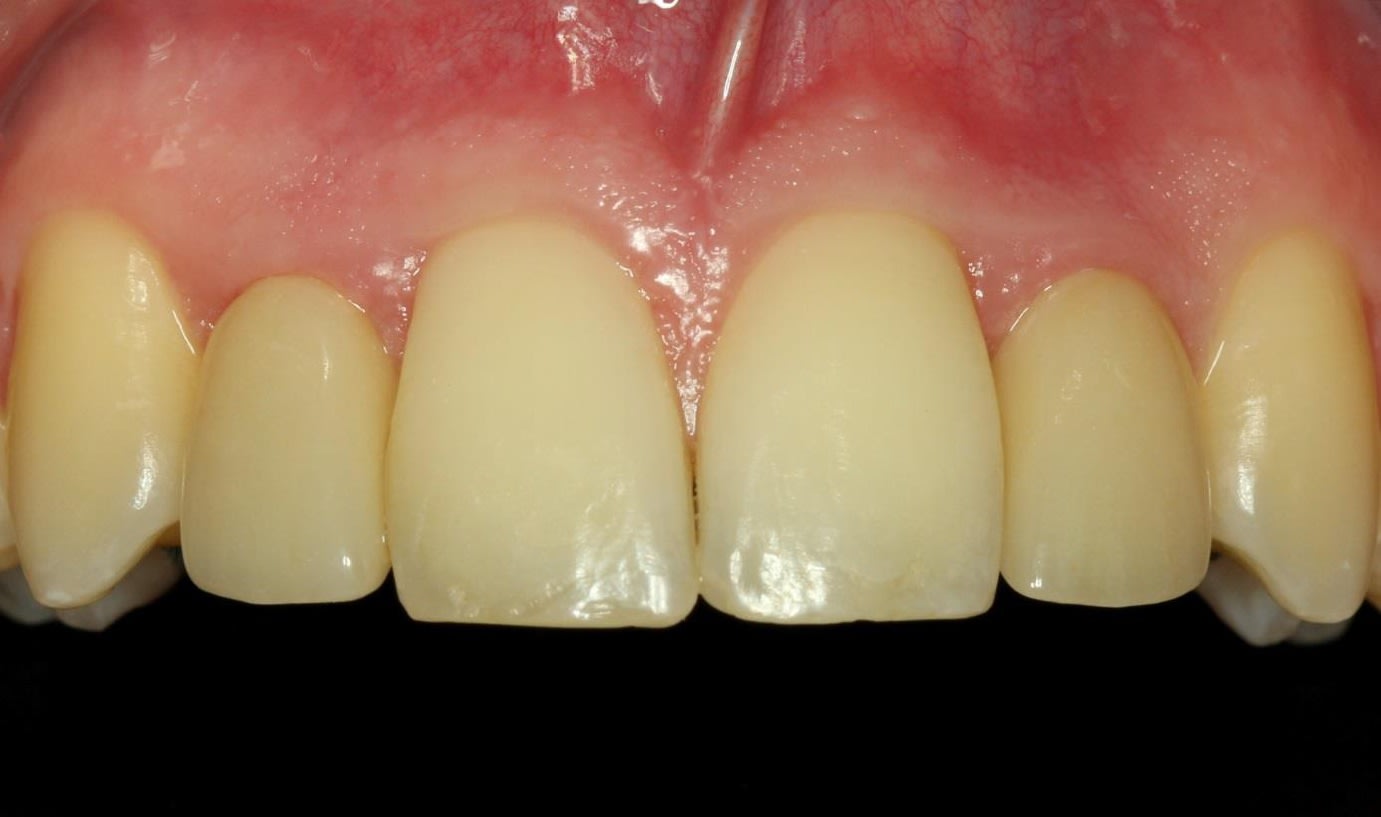

A healthy, nonsmoking, 19-year-old male patient presented with tooth agenesis of teeth Nos. 7 and 10 (Figure 1 and Figure 2). He underwent orthodontic treatment from August 2005 through September 2009 due to progeny tendency with a removable orthodontic appliance. Treatment with fixed orthodontic appliance was performed from November 2013 through April 2016.

Upon completion of the orthodontic therapy, the gaps between the roots of the adjacent teeth and the crowns of the adjacent teeth were restored. The patient was showing very limited gap widths and unfavorable interradicular space conditions. Initial marginal bone thickness in the gaps was approximately 4.5 mm (Figure 3) with apical thinning (Figure 4 and Figure 5).